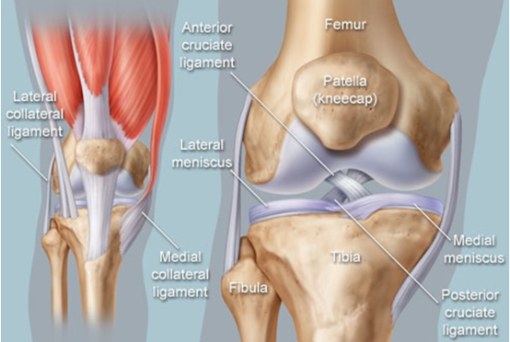

ACL Tears are now managed both operatively and non-operatively in Melbourne. Expert sports physiotherapy is essential following either surgery or post the bracing protocol, in order to achieve the strength and movement control that sport demands. ACL Physiotherapy in Melbourne can help you!